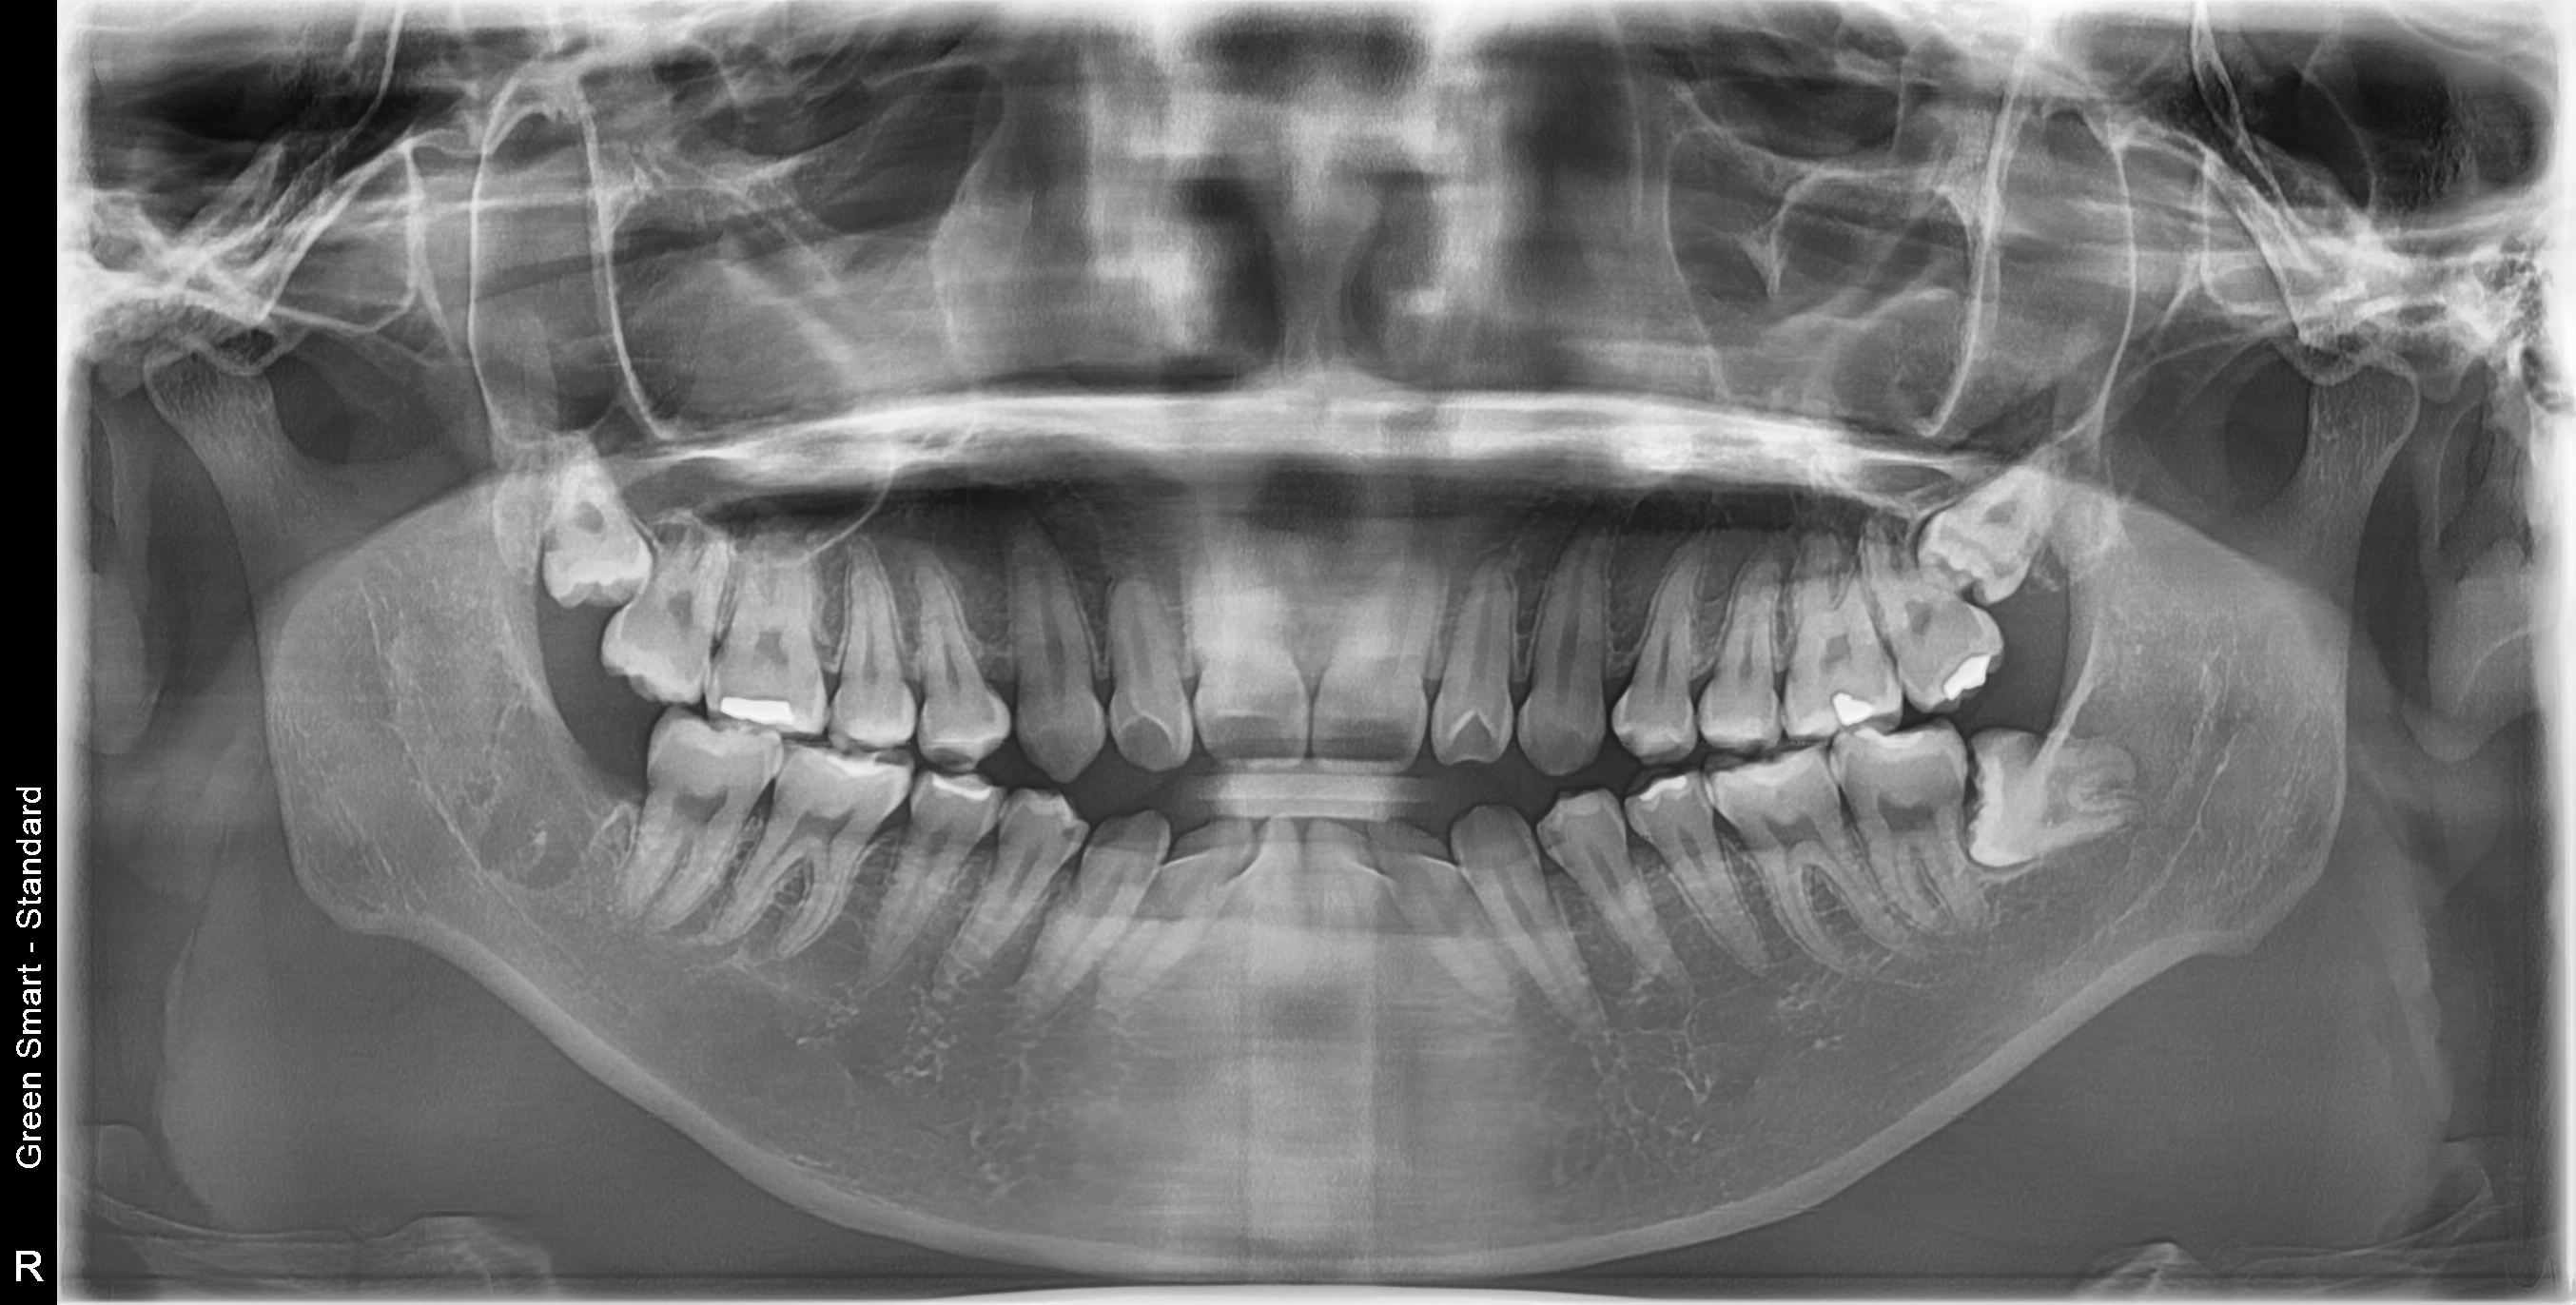

왜 지금 발치해야 할까요?

사랑니 방치 시 발생하는 문제

급성 염증

심한 통증과 얼굴 부종

인접 치아 충치

옆 치아까지 손상

턱관절 장애

만성 두통과 턱 통증

치열 불균형

교정 치료 필요

조기 발치의 장점

빠른 회복

젊을수록 회복 속도가 빠름

합병증 예방

염증 없을 땐 안전

비용 절감

문제 발생 전 처치

편안한 시술

연증 없어 마취가 잘 됨

참다참다 응급실 가시는 분들이 많아요

염증이 심해져서 새벽에 응급실을 찾는 환자분들이 매주 계십니다 미리 발치하면 이런 고통을 예방할 수 있습니다